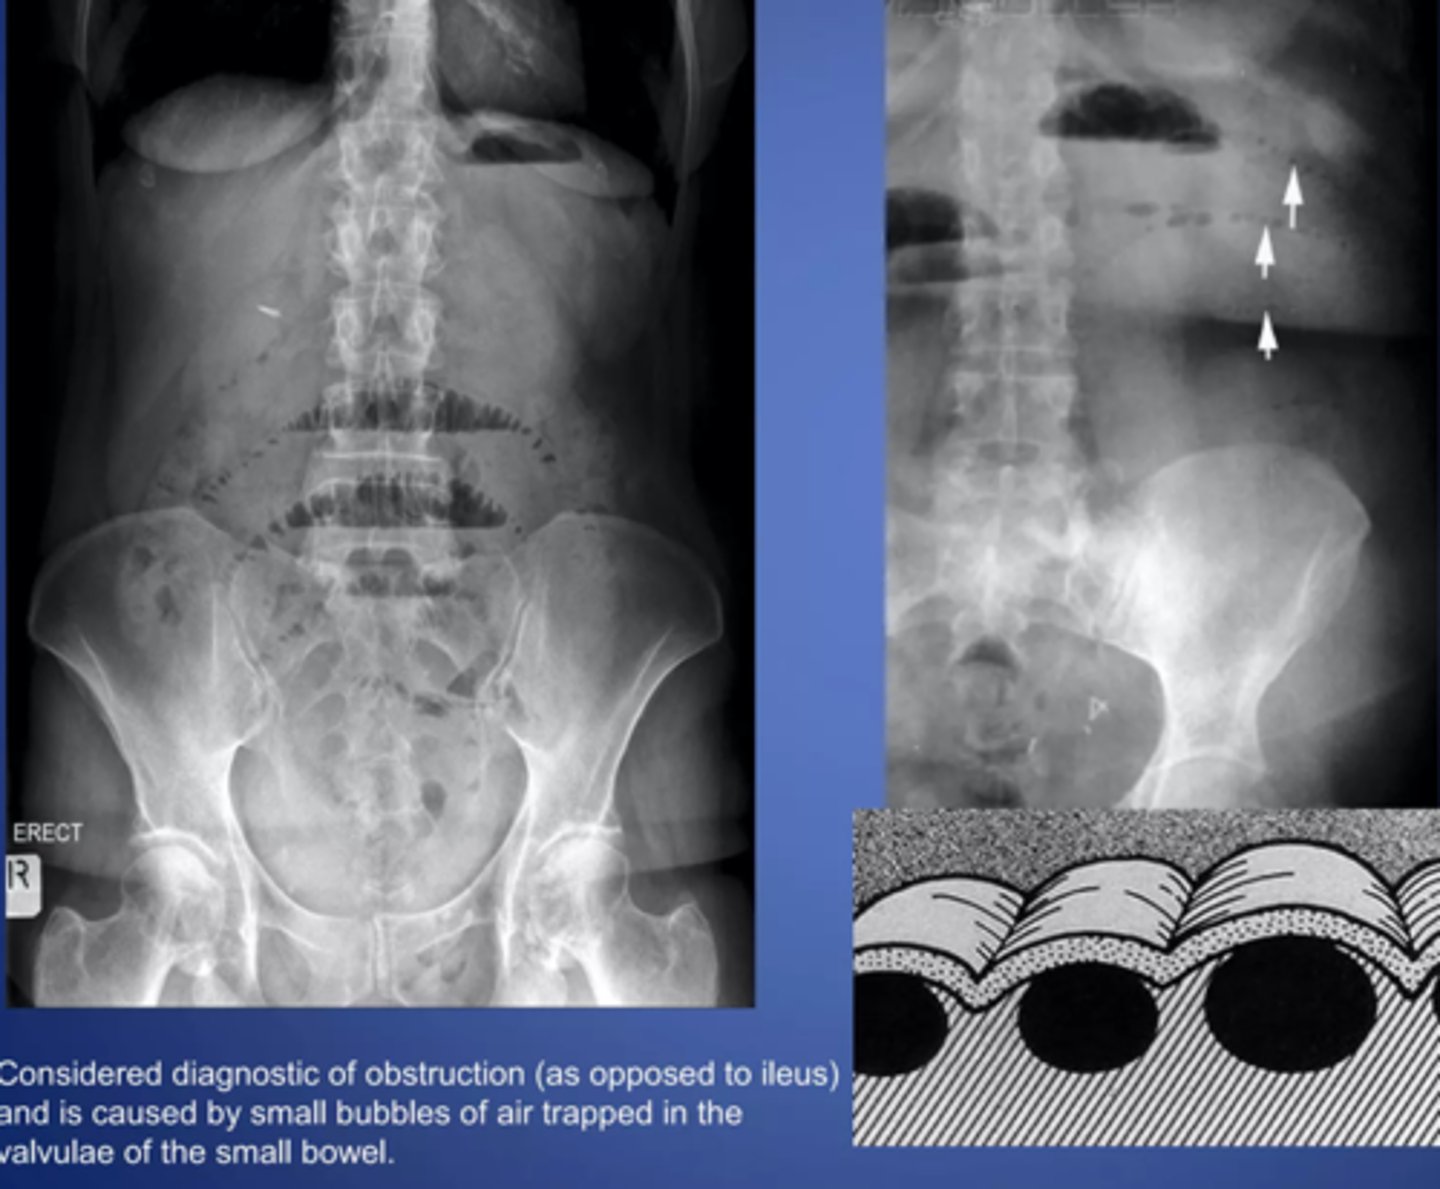

string of pearls sign- diagnostic of mechanical obstruction

stretch sign- small pockets of gas trapped bn valvulae conniventes within fluid filled bowel

valvulae connivente

thin, circumferential folds that extend across entire lumen of small bowel. Increased number in jejunum, appears like a stack of coins